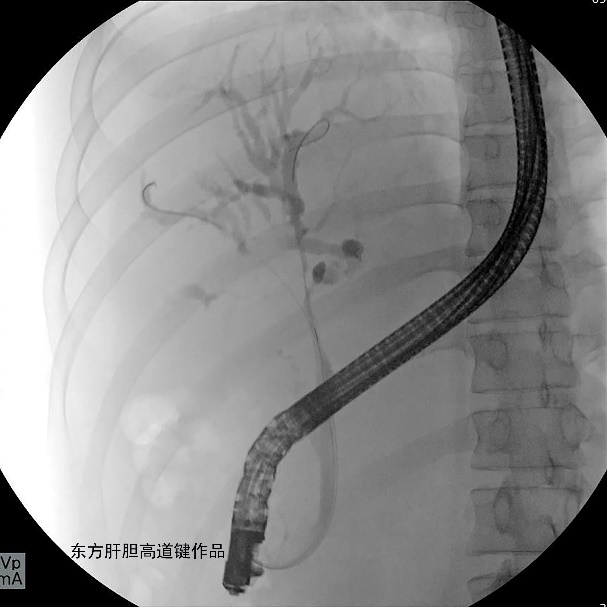

图D

图D:柱状气囊充分扩张胆管狭窄段;

图E:2根Zilver 8-80mm金属支架分别沿导丝插入右前与左内侧肝内胆管,完全释放右前肝内胆管的金属支架;

图F:再释放左内侧肝内胆管的金属支架,保留3根导丝在位,在原先留置于左外侧肝内胆管导丝的指引下,第四根导丝顺利从左内侧肝内胆管金属支架网眼穿过进入左外侧肝内胆管,但反复尝试,6F扩张导管无法通过金属网眼;

图G

图G:沿第三根位于左外侧肝内胆管导丝插入6F扩张导管顺利通过狭窄段进入左外侧肝内胆管;

图H:沿第三根导丝置入第三根金属支架并顺利释放;

图L:三根金属支架定位良好。